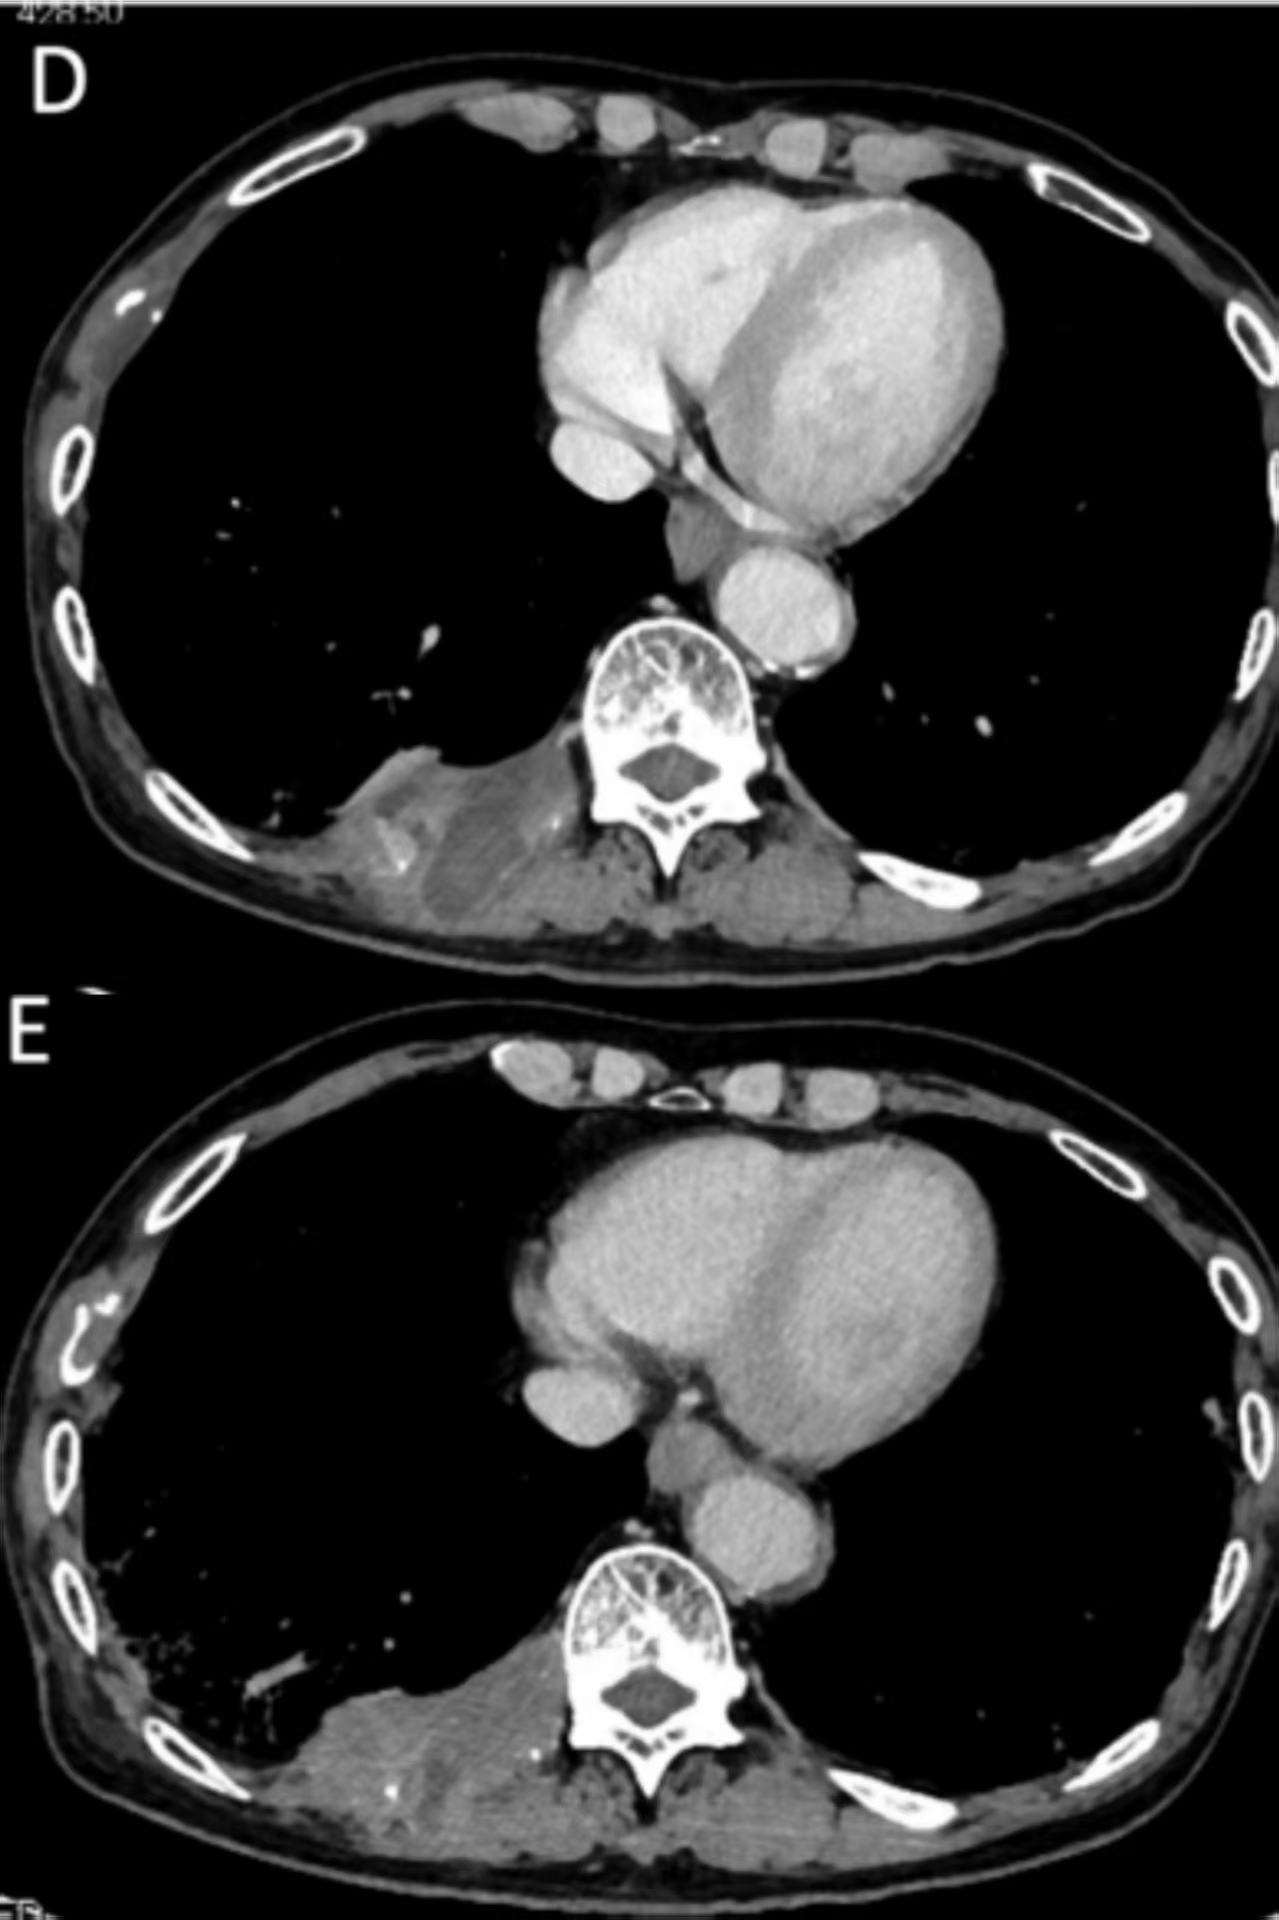

8月12日,《肝脏病学杂志》公布了一项重磅I期临床试验(NCT03132792)结果:靶向AFP(甲胎蛋白)的TCR-T疗法ADP-A2AFP在晚期肝癌患者中展现出显著疗效,甚至让部分患者肿瘤完全消失!